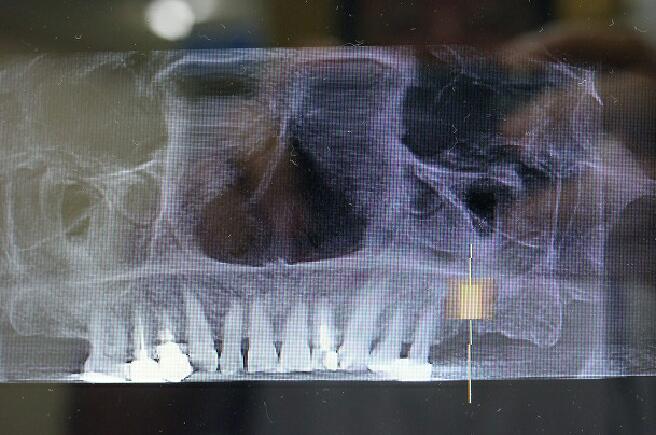

下記の症例では上顎のインプラントを実施するためCT(立体レントゲン)撮影致しました。

その部位の拡大エックス線像です

上顎には他の場所と違い上顎洞という頭を軽くするための空洞があり骨が2〜4ミリ程度しかなく、インプラントは大変困難です。

前方から見たエックス線像